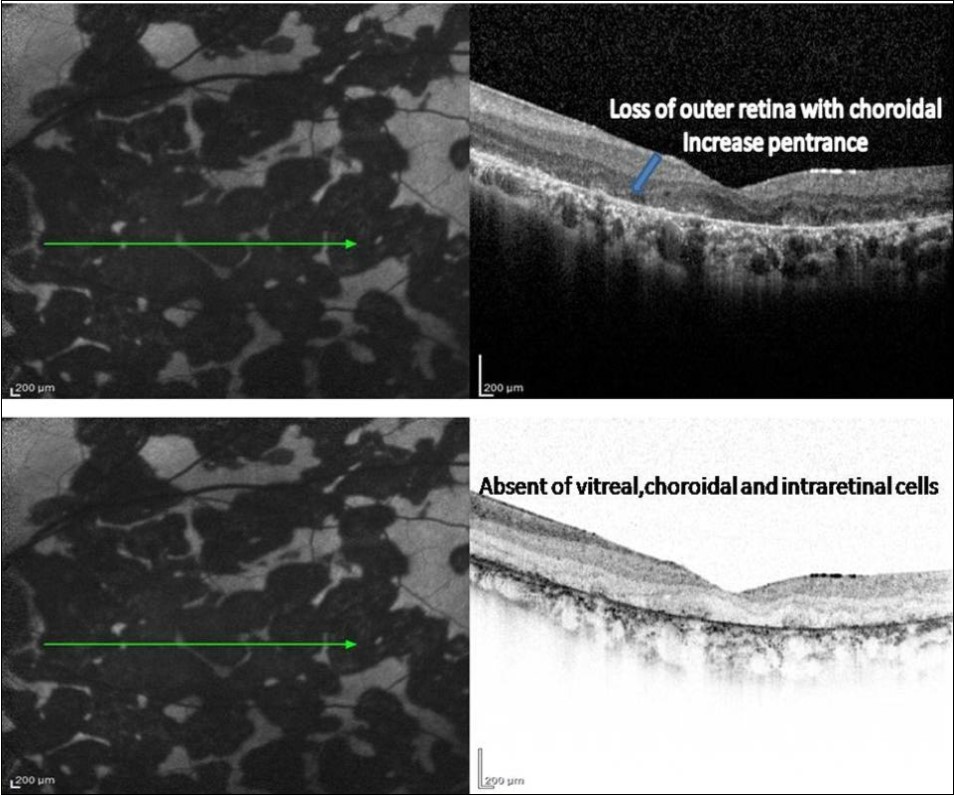

3. As the lesions healed further over the next 3–6 months, they appeared stippled with predominantly hypoautofluorescence. The SD-OCT scan showed loss of RPE, POST, IS/OS junction, and ELM with absent of the choroidal and intraretinal cells. The increased reflectance from the choroid persisted.

A 34-year-old male presented with decreased vision in Right eye since one and half month. On examination, the BCVA was 6/ 60 and 6/6 in the right and left eyes, respectively. Both eyes showed unremarkable anterior segment and multifocal lesions of active as well as inactive choroiditis in the posterior pole of Right eye and healed choroditis on left eye (Figure 1). Simultaneous FAF and SD-OCT imaging of the right eye revealed findings as explained in the “Results” Section (1.) (Figure 2). The tuberculin skin test was positive. He received four-drug antitubercular therapy with oral corticosteroids. About 2 weeks later, the lesions started to heal and appeared as described in “Results” Section (2.) (Figure 3). Three months later, the lesions healed further and appeared as explained in “Results” Section (3.) (Figure 4). Figure 5, Figure 6.

Figure 4.FAF (left) and corresponding eye-tracked SD-OCT image (right) of patient 1 healed stage of the left eye shows showed loss of RPE, POST, IS/OS junction, and ELM with increased reflectance from the choroidal layers. absent of the choroidal and intraretinal cells.